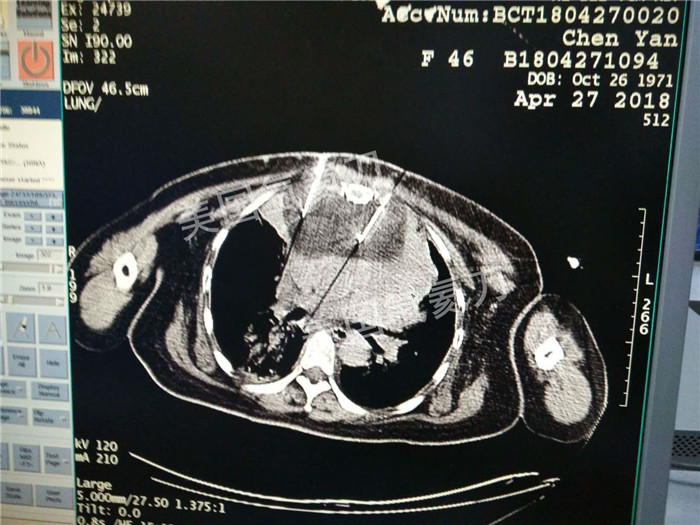

河北省中医院肿瘤科王利民主任胸腺19公分肿瘤氩氦刀手术

图片版权归美国氩氦刀所有,仅用于美国氩氦刀的宣传交流